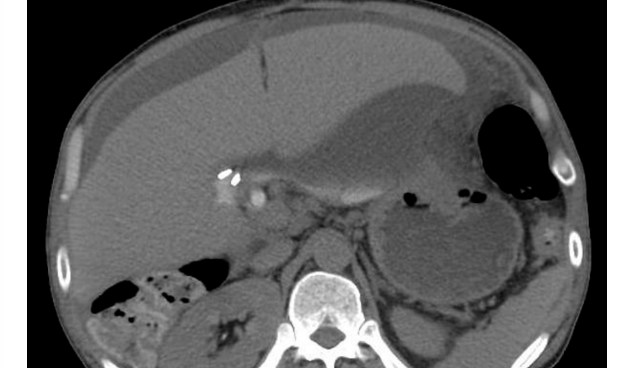

Efter en laparoskopisk kolecystektomi kan få ett gallläckge vilket ger smärtor med utstrålning. Kan även få abscess och blödning.

Frågeställning på rtg vid dessa symtom: